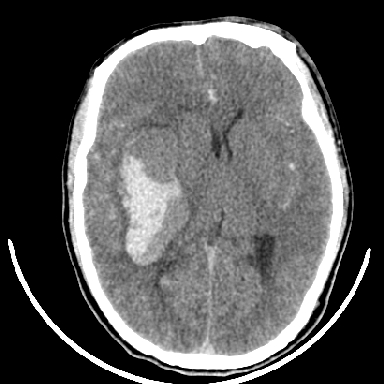

标题: CT6056:脑出血(血管畸形?) [打印本页]

标题: CT6056:脑出血(血管畸形?)

m 40突发头痛左侧偏瘫3小时

考虑高血压性脑出血,依据:

1是高血压性脑出血的好发部位,形态呈肾形,是高血压性脑出血的常见形状

2增强时占位效应加重了,考虑出血还没有停止

3病灶周围水肿不是太厉害,一般肿瘤出血水肿多非常明显

4病灶周围的‘软组织’影没有明显的强化

5至于脑血管畸形引起的出血,暂时没有看到明显的畸形血管影,也不太支持

支持右侧基底节脑出血

右侧基底节区脑出血.

支持右侧基底节区(主要为外囊区)原发性脑出血。

另附部分资料:“血液溢出血管外形成血肿,其内含有大量血红蛋白、血浆白蛋白,球蛋白,因这些蛋白对x线的吸收系数高于脑质,故ct呈现高密度阴影,ct值达40~90h,最初高密度灶呈非均匀一致性,中心密度更高,新鲜出血灶边缘不清。基底节区血肿多为“肾”型,内侧凹陷,外侧膨隆,因外侧裂阻力较小,故向外凸,其它部位血肿多呈尖圆形或不规则形”

术中抽出40ml陈旧血液,血肿底部似见一条索血管影